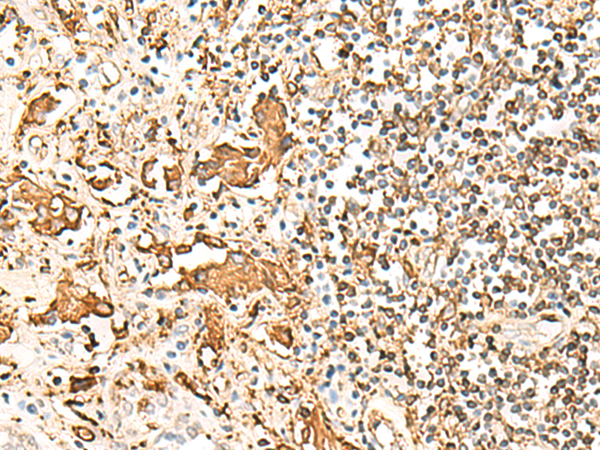

分类: 科研抗体货号: P09884别名: DR4; DRB4; HLA-DR4B应用: WB,IHC反应种属: Human

分类: 科研抗体货号: P09883别名: SS1; DRB1; HLA-DRB; HLA-DR1B应用: WB,IHC反应种属: Human